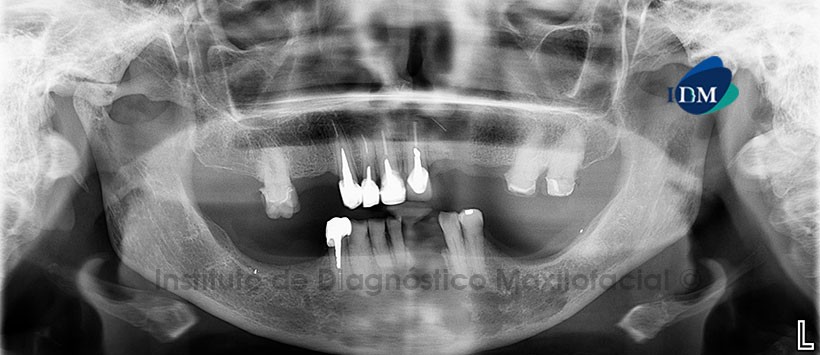

Paciente femenino, 66 años de edad, es referido al Instituto de Diagnostico Maxilofacial (IDM) para evaluación imagenológica por presentar signos clínicos de infección.

A la evaluación de la radiografía panorámica, se aprecia un proceso osteolítico de límites difusos localizado en la sínfisis, parasinfisis y cuerpo mandibular izquierdo, Además se aprecia un defecto ósea a nivel del reborde alveolar correspondiente a las piezas 3.1 y 3.2 (Figura 1).